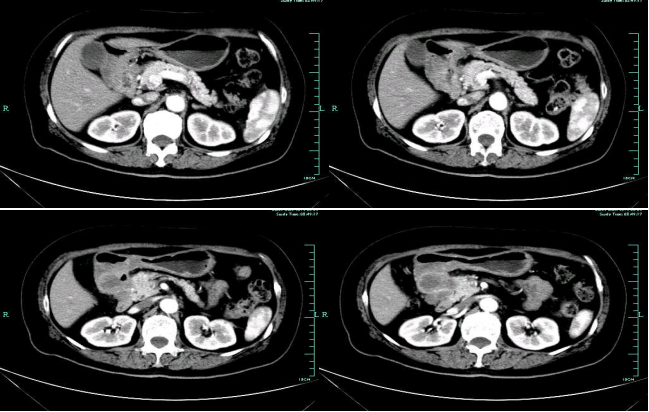

CT-T

CT-H1

MR-H1

影像学检查结果评估:cPD。

疗效评估:cPR